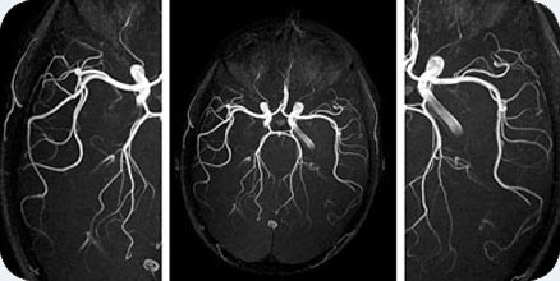

- Magistral arteriyaların MR-angioqrafiyası -əlavə kontrastlaşdırma aparılmadan damarların təsviri,

- Baş beyin damarlarının MR-angioqrafiyası (kontrast maddə olmadan)

- Boyun damarlarının MR-angioqrafiyası (kontrast maddə olmadan)